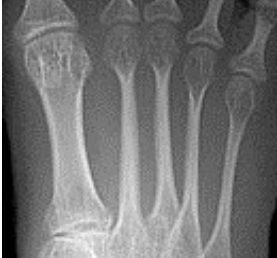

| What disease is this? | Rheumatoid arthritis |

| What disease is this? What does the arrow indicate? | Rheumatoid arthritis. Arrow = Bone erosion secondary to inflammation of retrocalcaneal bursa. |